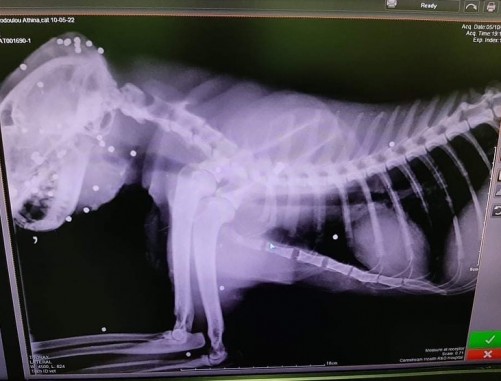

Τα κουτάβια, εξετάστηκαν από κτηνίατρο και είναι μόλις δύο μηνών